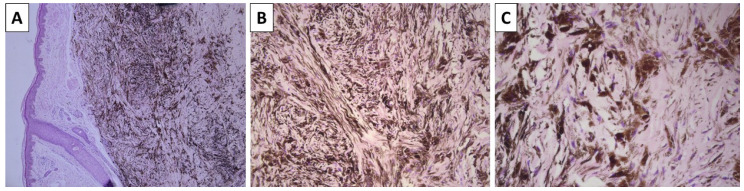

Background and Clinical Significance: Blue nevi are a dubious pigmented lesion. While somewhat common throughout the population, they are significantly less common than other melanocytic neoplasms, and both their morphology and development bring them closer to true hamartomas than neoplasms. An exceedingly rare occurrence is the development of melanoma from a preexisting blue nevus. This nosological unit, defined as melanoma arising in a blue nevus, also known as malignant blue nevus, blue naevus-like melanoma, melanoma ex-blue naevus, and melanoma mimicking cellular blue naevus, is required to either originate from an area of previously excised blue nevus or have a blue nevus remnant adjacent to it. Due to the spindle cell morphology of melanoma arising in blue nevus, the terminology is often misused by some authors to include spindle cell melanomas, which exhibit a distinct pathogenesis and, although morphologically similar, have differing molecular profiles as well. Case presentations: The following manuscript discusses comparative morphological features in a case series of blue nevi and melanoma arising in blue nevi. Discussion: Blue nevi present with unique morphological features, with melanomas originating from them having a unique molecular pathology profile, which significantly differs from other cutaneous melanomas and is closer to that of uveal melanomas.